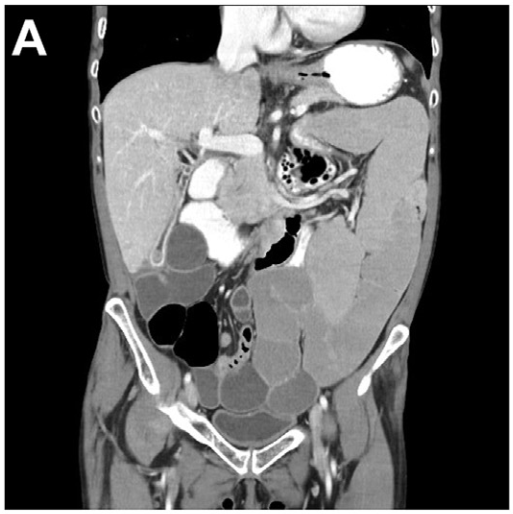

- 1型自身免疫性胰腺炎的药物治疗 1型自身免疫性胰腺炎是一种以胰腺慢性炎症和纤维化为主要特征的慢性炎症性疾病,经典治疗手段如糖皮质激素、单克隆抗体及免疫调节剂在自身免疫性胰腺炎诱导治疗和维持治疗中起到关键作用……